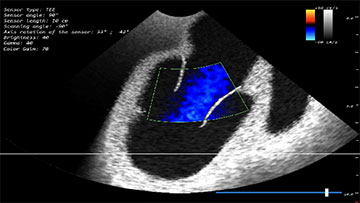

Модуль по трансэзофагеальному УЗИ сердца

- Обучающий модуль по трансэзофагеальному ультразвуковому исследованию сердца